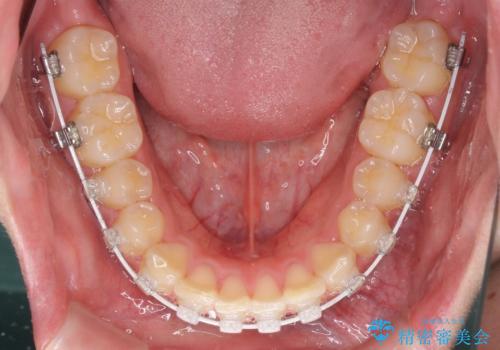

- 審美装置

マウスピース矯正の自己管理が面倒とのことで、ワイヤー矯正により治療を行うこととしました。

インビザラインでの治療も可能でしたが、深い咬み合わせと奥歯の咬み合わせを改善するにあたり、ワイヤー矯正の方が治療期間を短縮できると判断し、ワイヤー矯正をお勧めしました。

結果として、1年かからずに奥歯の咬み合わせを改善することができました。